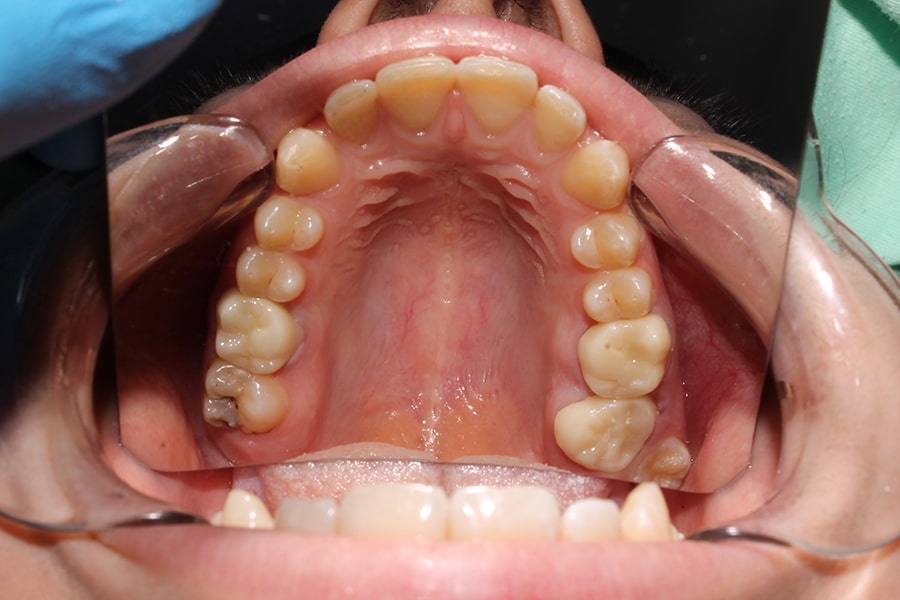

Clasificación de los dientes según su tipo

En la cavidad oral humana, los dientes se clasifican en cuatro tipos principales: incisivos, caninos, premolares y molares. Cada uno cumple una función en el proceso de masticación y en otras actividades como el habla y la estética facial. Esta diversidad asegura que los alimentos se procesen de manera eficiente antes de la digestión.

Molares

Los molares están ubicados en la parte posterior de la boca y son los dientes más grandes y fuertes. Los adultos tienen 12 molares, incluidos los terceros molares o muelas del juicio.

- Características: poseen una superficie plana y extensa con cúspides diseñadas para soportar grandes fuerzas masticatorias.

- Función: los molares son responsables de moler y triturar los alimentos en partículas pequeñas, facilitando la deglución y el proceso digestivo.

- Corona: es amplia y plana, con múltiples cúspides (habitualmente cuatro o cinco) diseñadas para triturar alimentos. El esmalte es más grueso en la superficie oclusal para soportar la presión de la masticación.

- Raíz: los molares superiores tienen tres raíces (dos bucales y una palatina), mientras que los inferiores suelen tener dos raíces. Esta estructura asegura una sujeción firme para soportar las fuerzas intensas de la masticación.

- Pulpa dental: la cámara pulpar es extensa y está ramificada, lo que refleja la complejidad de las cúspides y raíces. Esto también hace que los tratamientos de conducto en molares sean más complejos.